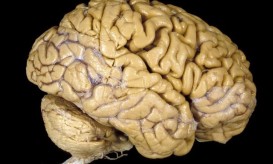

Ο ανθρώπινος εγκέφαλος είναι ένα μυστήριο από μόνο του. Οι επιστήμονες έχουν προσπαθήσει πολλές φορές να καταλάβουν, και να...